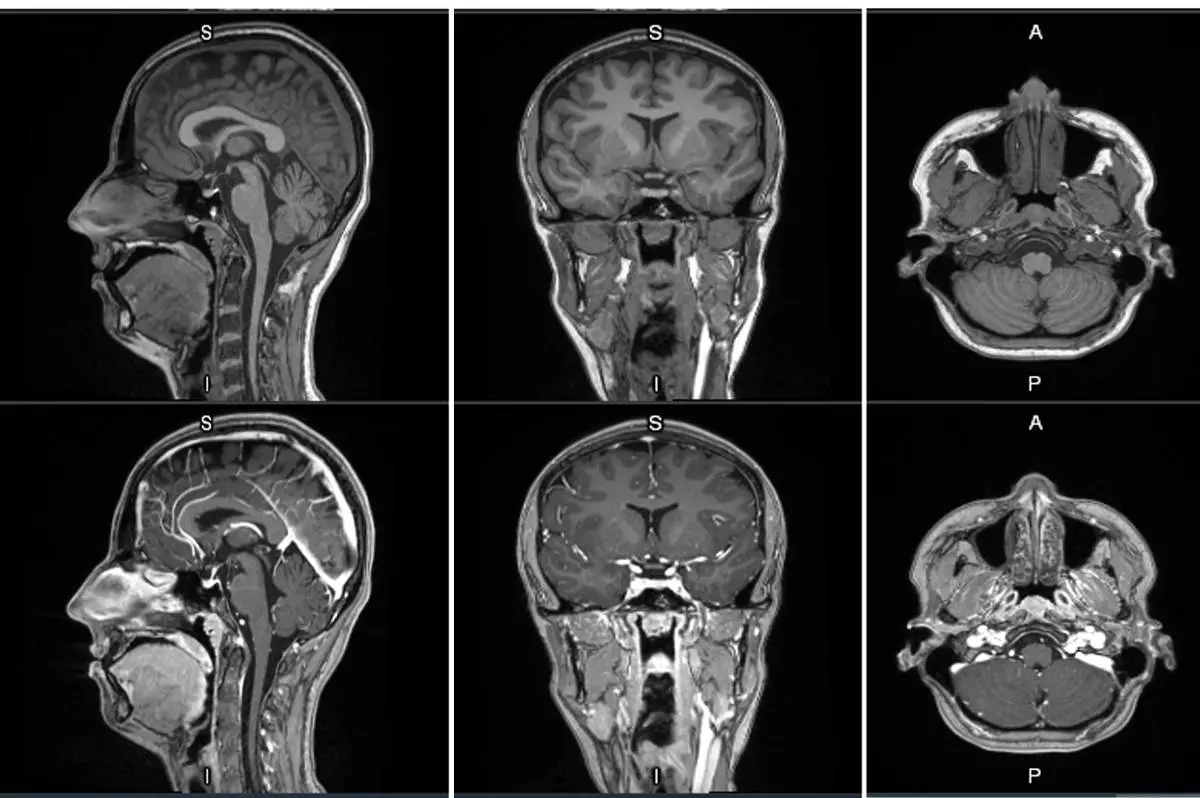

First-in-human contrast enhanced MRI images with GE HealthCare's mangaciclanol

GE HealthCare (Nasdaq: GEHC) today announced the first patient has been dosed in the international, multi-center Phase 2/3 LUMINA clinical trial of its manganese-based magnetic resonance imaging (MRI) contrast agent, mangaciclanol, at Mayo Clinic in Rochester, Minnesota. Mangaciclanol, if approved, could offer an alternative to – or even replace – gadolinium-based MRI contrast agents, the current standard of care. The investigational agent has been granted Fast Track designation by the U.S. Food and Drug Administration (FDA) for use in adults and pediatric patients aged 2 years and older with MRI to detect and visualize lesions with abnormal vascularity in the central nervous system and the body. FDA Fast Track designation expedites the review of new therapeutics and medical imaging agents that have the potential to address significant unmet patient needs.

MRI contrast agents enhance the visualization of abnormal structures or lesions during imaging procedures and help clinicians better distinguish between healthy and diseased tissue. Mangaciclanol is intended for general-purpose MR imaging and demonstrates comparable relaxivity (the ability to enhance signal intensity) to market-leading gadolinium-based agent, gadobutrol, with early clinical images suggesting similar diagnostic capability. Unlike gadolinium, which is a rare-earth metal, manganese is present in our food, and is an endogenous element, naturally occurring and autoregulated in the body. The macrocyclic ‘cage-like’ structure of mangaciclanol lessens the possibility of retention.